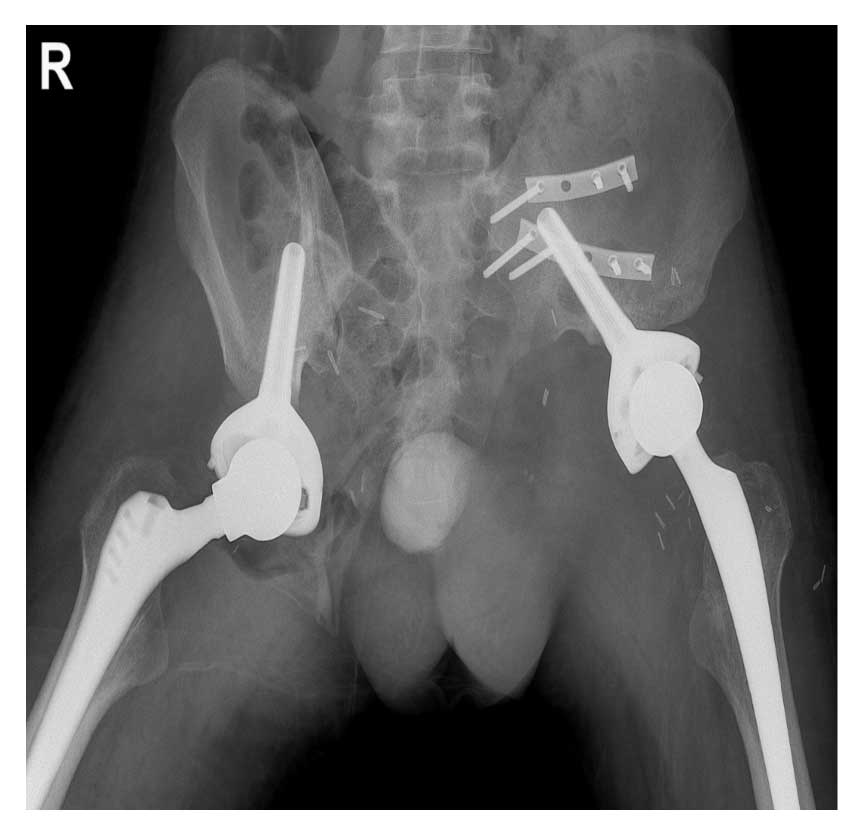

Ameliyat Sonrası: Röntgende iki taraflı internal hemipelvektomi sonrası Lumic protez ile rekonstrüksiyon uygulanımı görülmekte.